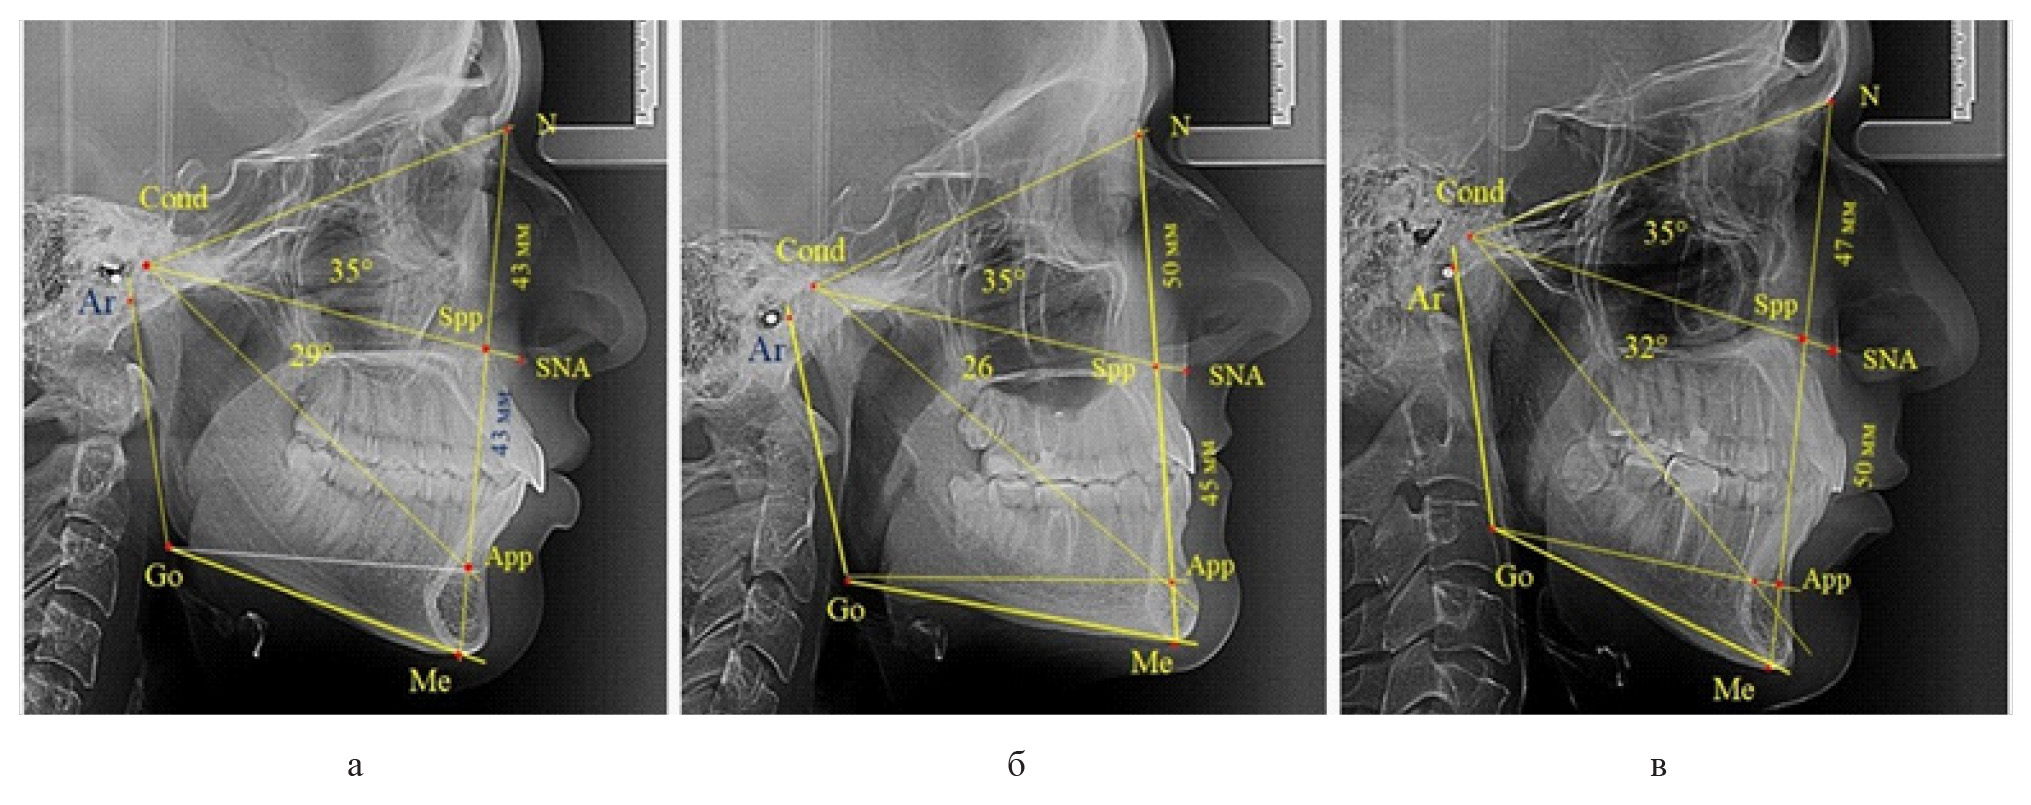

Среди пациентов с аномалиями челюстно-лицевой области в вертикальном направлении у 24 человек определялась глубокая резцовая окклюзия/дизокклюзия (рис. 5).

Рис. 5. Варианты ТРГ с оптимальными размерами носового отдела и оптимальными (а) и укороченными (б) размерами гнатической части лица

При этом только в двух случаях [(8,33 ± 5,64) %], параметры носового и гнатического отдела соответствовали норме. У 9 человек [(37,59 ± 9,88) %], при оптимальных параметрах назального отдела отмечалось уменьшение высоты гнатического отдела, вплоть до патологических показателей.

У людей с глубокой резцовой окклюзией нередко отмечалось изменение параметров носового отдела лица. Так, в 7 случаях было выявлено снижение параметров как носового, так и гнатического отделов лица. У 5 человек [(20,83 ± 8,28) %], отмечалось уменьшение носового отдела лица при оптимальных параметрах гнатического отдела.

В одном случае [(4,17 ± 4,08) %], определялось патологическое увеличение назального отдела лица при уменьшении гнатической его части. Некоторые варианты ТРГ пациентов с глубокой резцовой окклюзией представлены на рис. 6.

Рис. 6. Варианты ТРГ с уменьшенными размерами носового отдела и оптимальными (а) и укороченными (б) размерами гнатической части лица при глубокой резцовой окклюзии